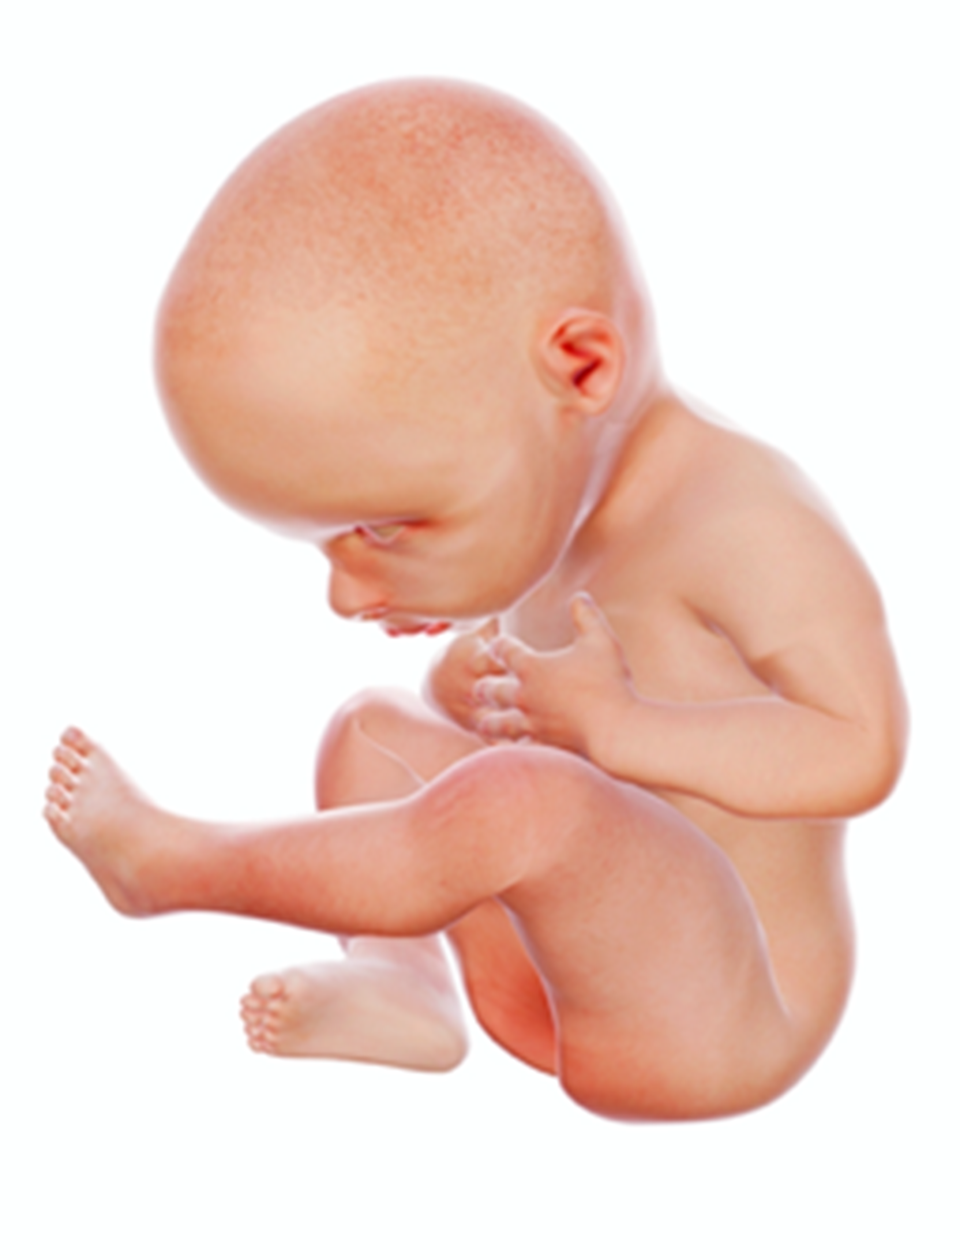

8 miesiąc | 45–50 cm | Intensywnie rozwija się podskórna tkanka tłuszczowa, która chroni płód przed utratą ciepła. Szybko rozwija się układ oddechowy. Płód w związku z brakiem miejsca przyjmuje pozycję embrionalną (pochylona głowa, zgięte kończyny przyciśnięte do tułowia). ![]() Źródło: Englishsquare.pl Sp. z o. o., licencja: CC BY-SA 3.0. | |